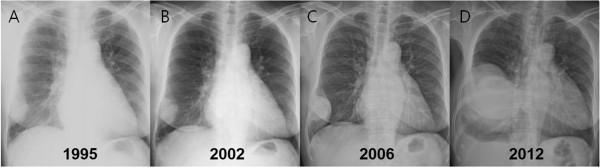

Although a solitary fibrous tumor of the pleura (SFTP) is a rare disease, and usually has a benign course, it has a malignant potential. We report a case of malignant SFTP treated surgically. A 75-year-old female was admitted with a chief complaint of hemoptysis of two weeks duration. Computed tomography of the chest imaged a large mass in the right hemithorax, which compressed adjacent organs; however, there was no evidence of invasion. We reviewed the patient's medical records and found that the mass had been presented for 17 years. Complete resection was achieved through a right thoracotomy and histopathologic examination confirmed a malignant SFTP.

尽管胸膜孤立性纤维瘤(SFTP)是一种罕见疾病,且通常病程呈良性,但它具有恶变潜能。我们报告一例经手术治疗的恶性SFTP病例。一名75岁女性因持续两周的咯血为主诉入院。胸部计算机断层扫描显示右半胸有一个大肿块,该肿块压迫相邻器官;然而,没有侵袭的证据。我们查阅了患者的病历,发现该肿块已存在17年。通过右胸切开术实现了完整切除,组织病理学检查证实为恶性SFTP。